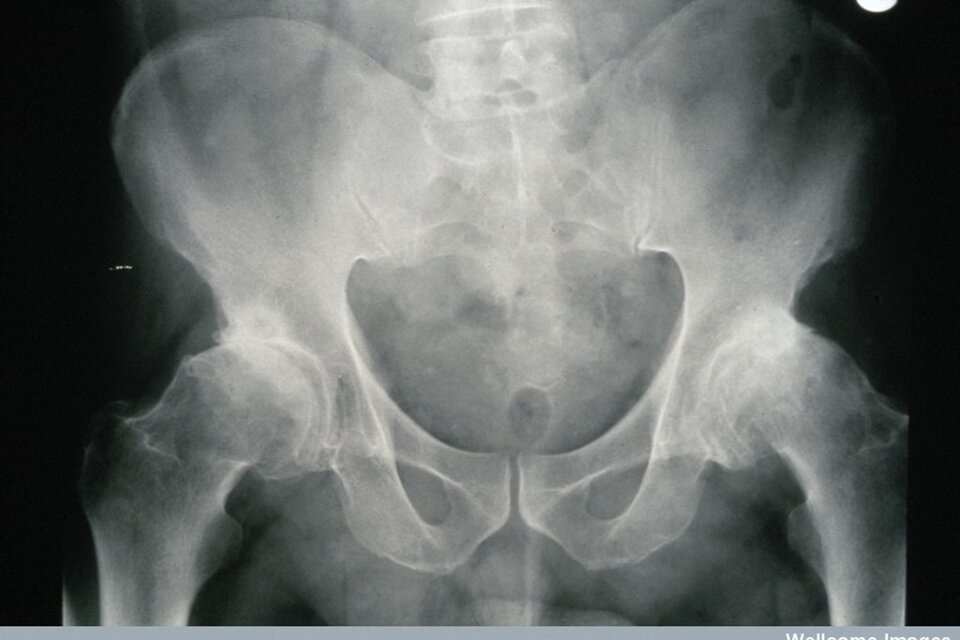

zwiększone ryzyko złamań kości, będące skutkiem postępującej osteoporozy.